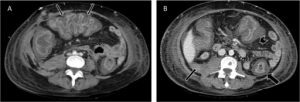

Pseudomembranous colitis with (A) Accordion sign in transverse colon (thin arrows). (B) Colonic wall thickness, target sign (thick arrow), peritoneal fluid (thin arrow) and pericolonic fat stranding (arrowhead).